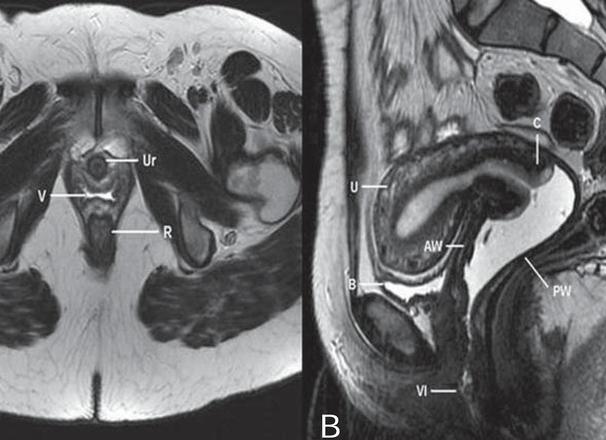

МРТ молочных желез проводится чаще всего для выявления различных новообразований в них, а также для диагностики патологии в этой части тела. Использование этого метода позволяет установить достоверный диагноз даже в спорных случаях.